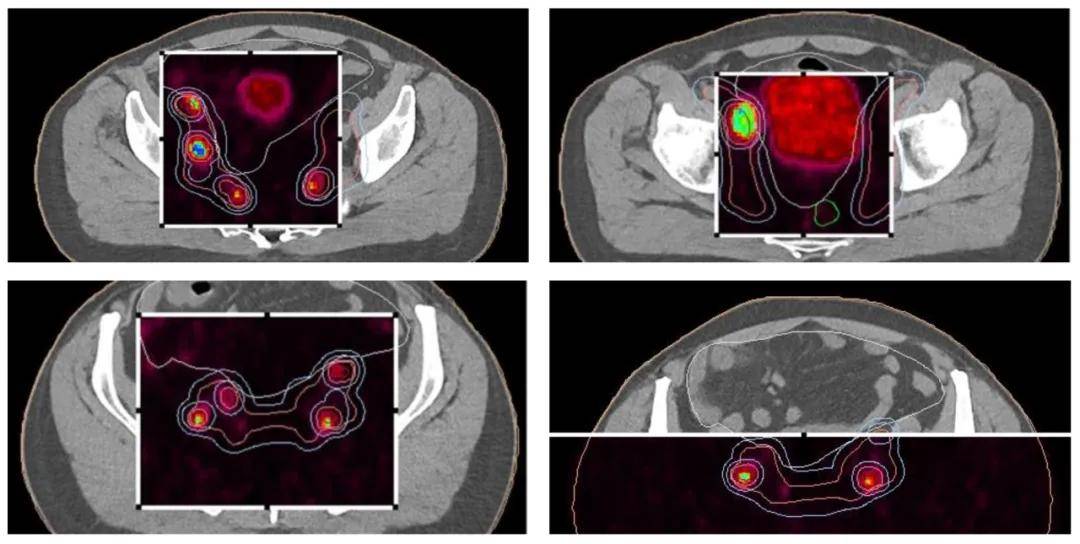

本研究提出一种针对广泛转移性前列腺癌的综合治疗方案。一名57岁男性患者因PSA水平升高入院 (图1),经全面评估后,先接受比卡鲁胺治疗,并通过PET/PSMA等影像学检查明确癌症分布。随后,患者接受雄激素剥夺疗法及多西他赛化疗。因疾病仍有活动迹象,故采用放疗巩固,包括针对前列腺和转移淋巴结的远程放疗 (图2) 及前列腺的高剂量率近距离放疗 (图3)。

患者初始PSA高达280 ng/mL,前列腺活检确诊为腺癌,Gleason评分7,WHO分级3。CT显示广泛盆腔淋巴结转移,PET/PSMA影像 (图4) 揭示前列腺及淋巴结高代谢活性。患者被诊断为cT2N1M1a期前列腺癌。经多西他赛化疗,PSA水平有所下降,但CT仍示广泛转移。随后进行放疗,PET-CT (图5) 显示前列腺及淋巴结仍具活性。放疗后,患者PSA降至检测限下,实现完全生化缓解,此疗效经随访影像及临床评估确认。